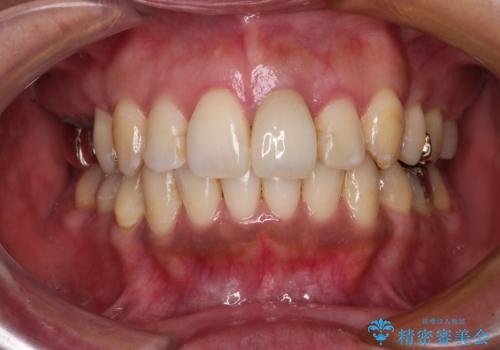

八重歯で口元が膨れている ワイヤー装置での抜歯矯正